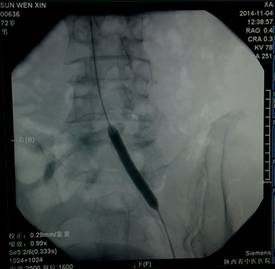

术中对左侧骼总动脉狭窄处进行倾囊扩张 |

术中对右侧骼总动脉蔽塞处进行球囊扩张 |